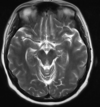

Q

35 anos, Masculino

A

Craniofaringioma adamantinomatoso

Craniofaringioma adamantinomatoso Crianças Lesão suprasselar com componente sólido e cístico; lobulado; calcificação anelar ou nodular presente em quase TODOS os craniofaringeomas pediátricos; Componente cístico proeminente e componente sólido pequeno, mas com realce.